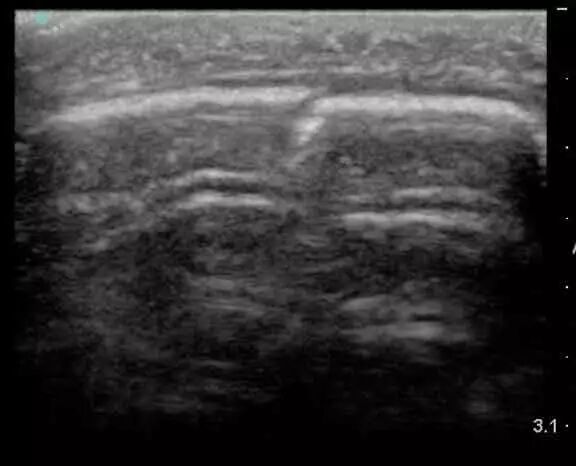

肱骨内上髁骨折超声影像

肌骨超声,具备实时动态成像、操作简便高效、无辐射、双侧对比观察、互动性好、可实施引导介入治疗等优势,已被越来越多地应用于肌肉骨骼系统及软组织疾病的诊断治疗中。超声波不能穿透骨骼,仅能显示探头侧的骨皮质,骨皮质在正常骨骼声像图上表现为连续、规则的线状明亮强回声,因此可以利用这一特征对骨折进行判断。